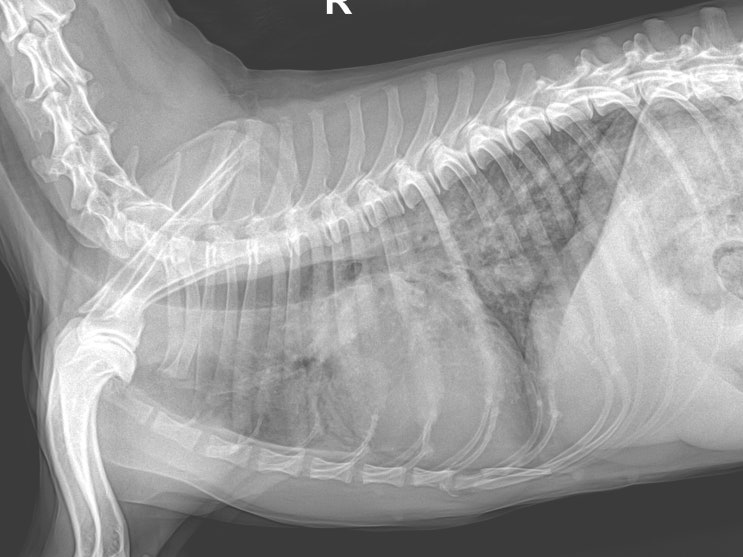

15살 강아지 심장병 폐수종 치료 후기 / 과거에 심장사상충 치료한 노령견 심장병 관리 / 반려견 폐수종 증상, 치료 전문 동물병원 / 강아지 호흡곤란, 호흡이상, 호흡수 증가

안녕하세요~ 굿파파 수의사입니다. 오늘은 근로자의 날이네요~ 번개가 치고, 비가 내리기 시작하네요 따뜻...